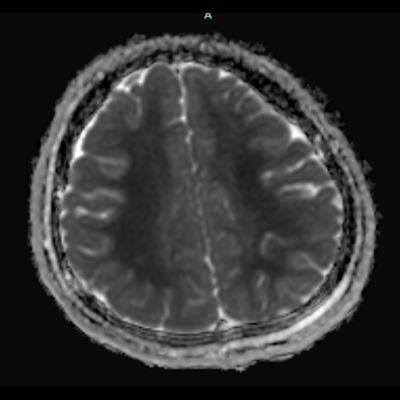

- A) Bilateral serebral kortekste (oklar) ve bazal ganglionlarda (oklar) yaygın DAG hiperintens, ADC hipointens difüzyon kısıtlamaları görülüyor.

- T2A / FLAIR serilerde beyaz cevherde özellikle sentrum semiovalede diffüz yüksek sinyal görülür. Subkortikal U lifleri sıklıkla korunur.

- DAG görüntülemede sıklıkla belirgin difüzyon kısıtlaması görülür.